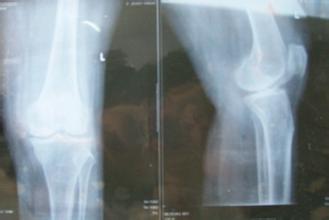

对于中老年人来说,骨质增生是无法避免的老年疾病。当骨质增生发病时,关节软骨、椎间盘、韧带等软组织会发生变性、退化,关节边缘形成骨刺,滑膜变得肥厚,出现骨破坏,继而引起骨质增生。严重患者导致关节变形、关节疼痛和活动受限等不良后果。因此,对于大家来说,要注意日常生活中的保健。》》》专家在线,点击免费咨询、预约